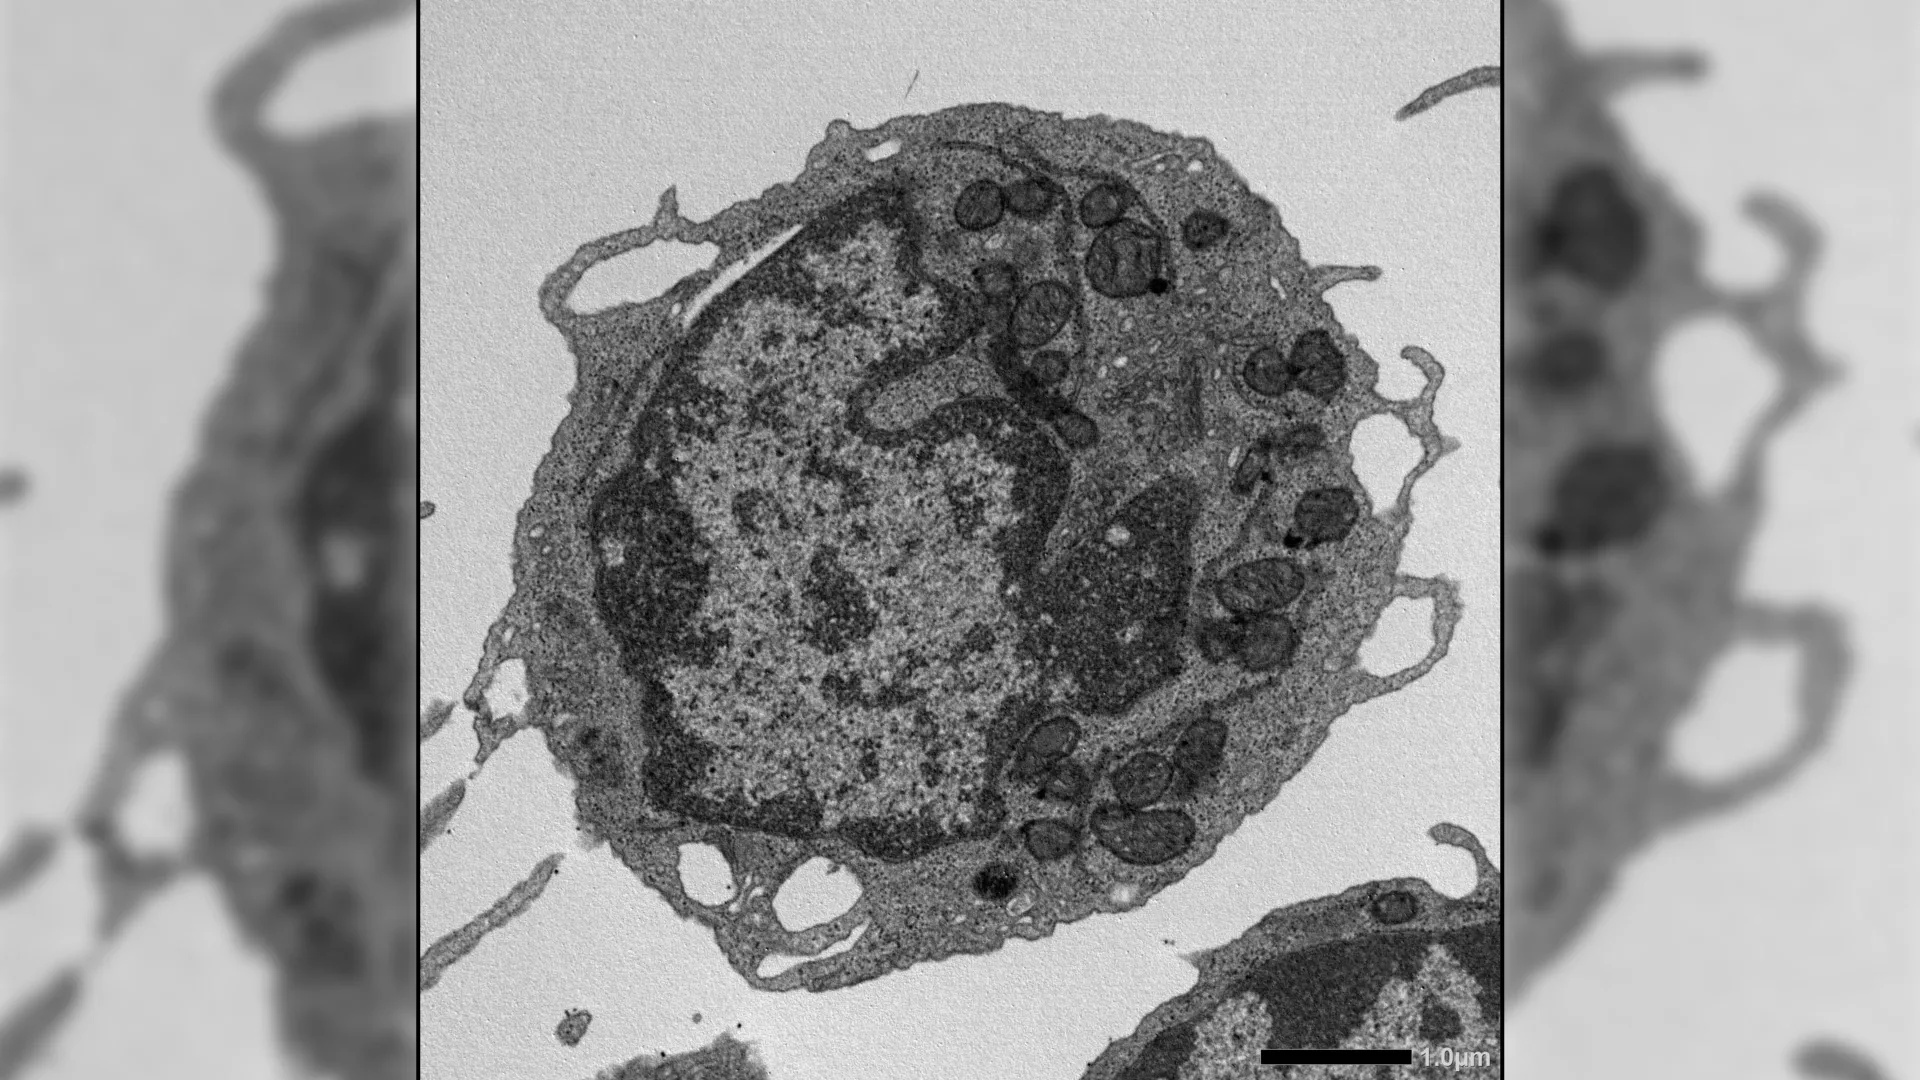

A investigação focou na proteína MLKL, usualmente associada à necroptose, uma forma de morte celular programada. Contraintuitivamente, os cientistas observaram que a ativação da MLKL em CTHs não resultava na morte dessas células, mas sim em um dano significativo às suas mitocôndrias – as "usinas de energia" celulares. Este dano mitocondrial, por sua vez, foi diretamente ligado à perda de funcionalidade das CTHs, incluindo sua capacidade de autorrenovação e a produção equilibrada de células imunes.